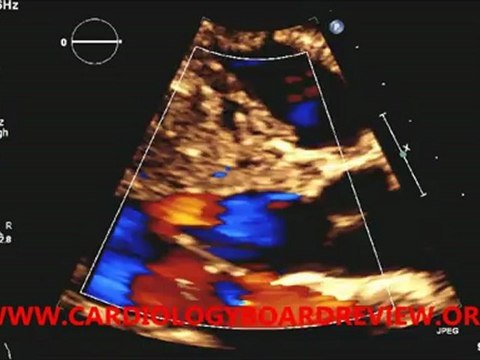

Systolic, anterior, motion, mitral, valve